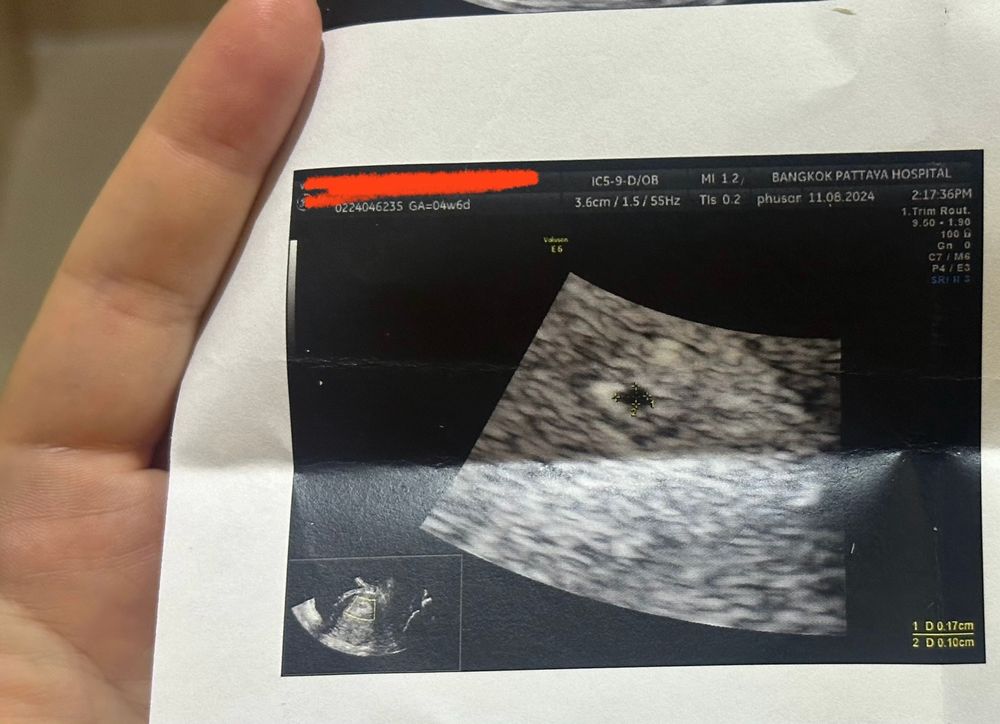

Помогите разобраться с первым узи 🙏🏾🙏🏾🙏🏾 ничего не понимаю - на момент узи (вчера было 5 акушерских недель) хгч растет хорошо говорят - но я так поняла что мешочек всего 1,3 мм 🫤 это ведь очень мало для 5ти недель ((( может я не так поняла ((( ничего не пойму по этому описанию и узи (я за границей) немног сложно((

Ещё рано что-то говорить в 5 недель.

Плодное яйцо есть и мешочек вполне хороший. Сходите еще через недели 2, а лучше 3, и должно быть сердечко)